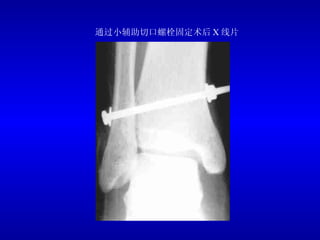

通过小辅助切口螺栓固定术后 X 线片